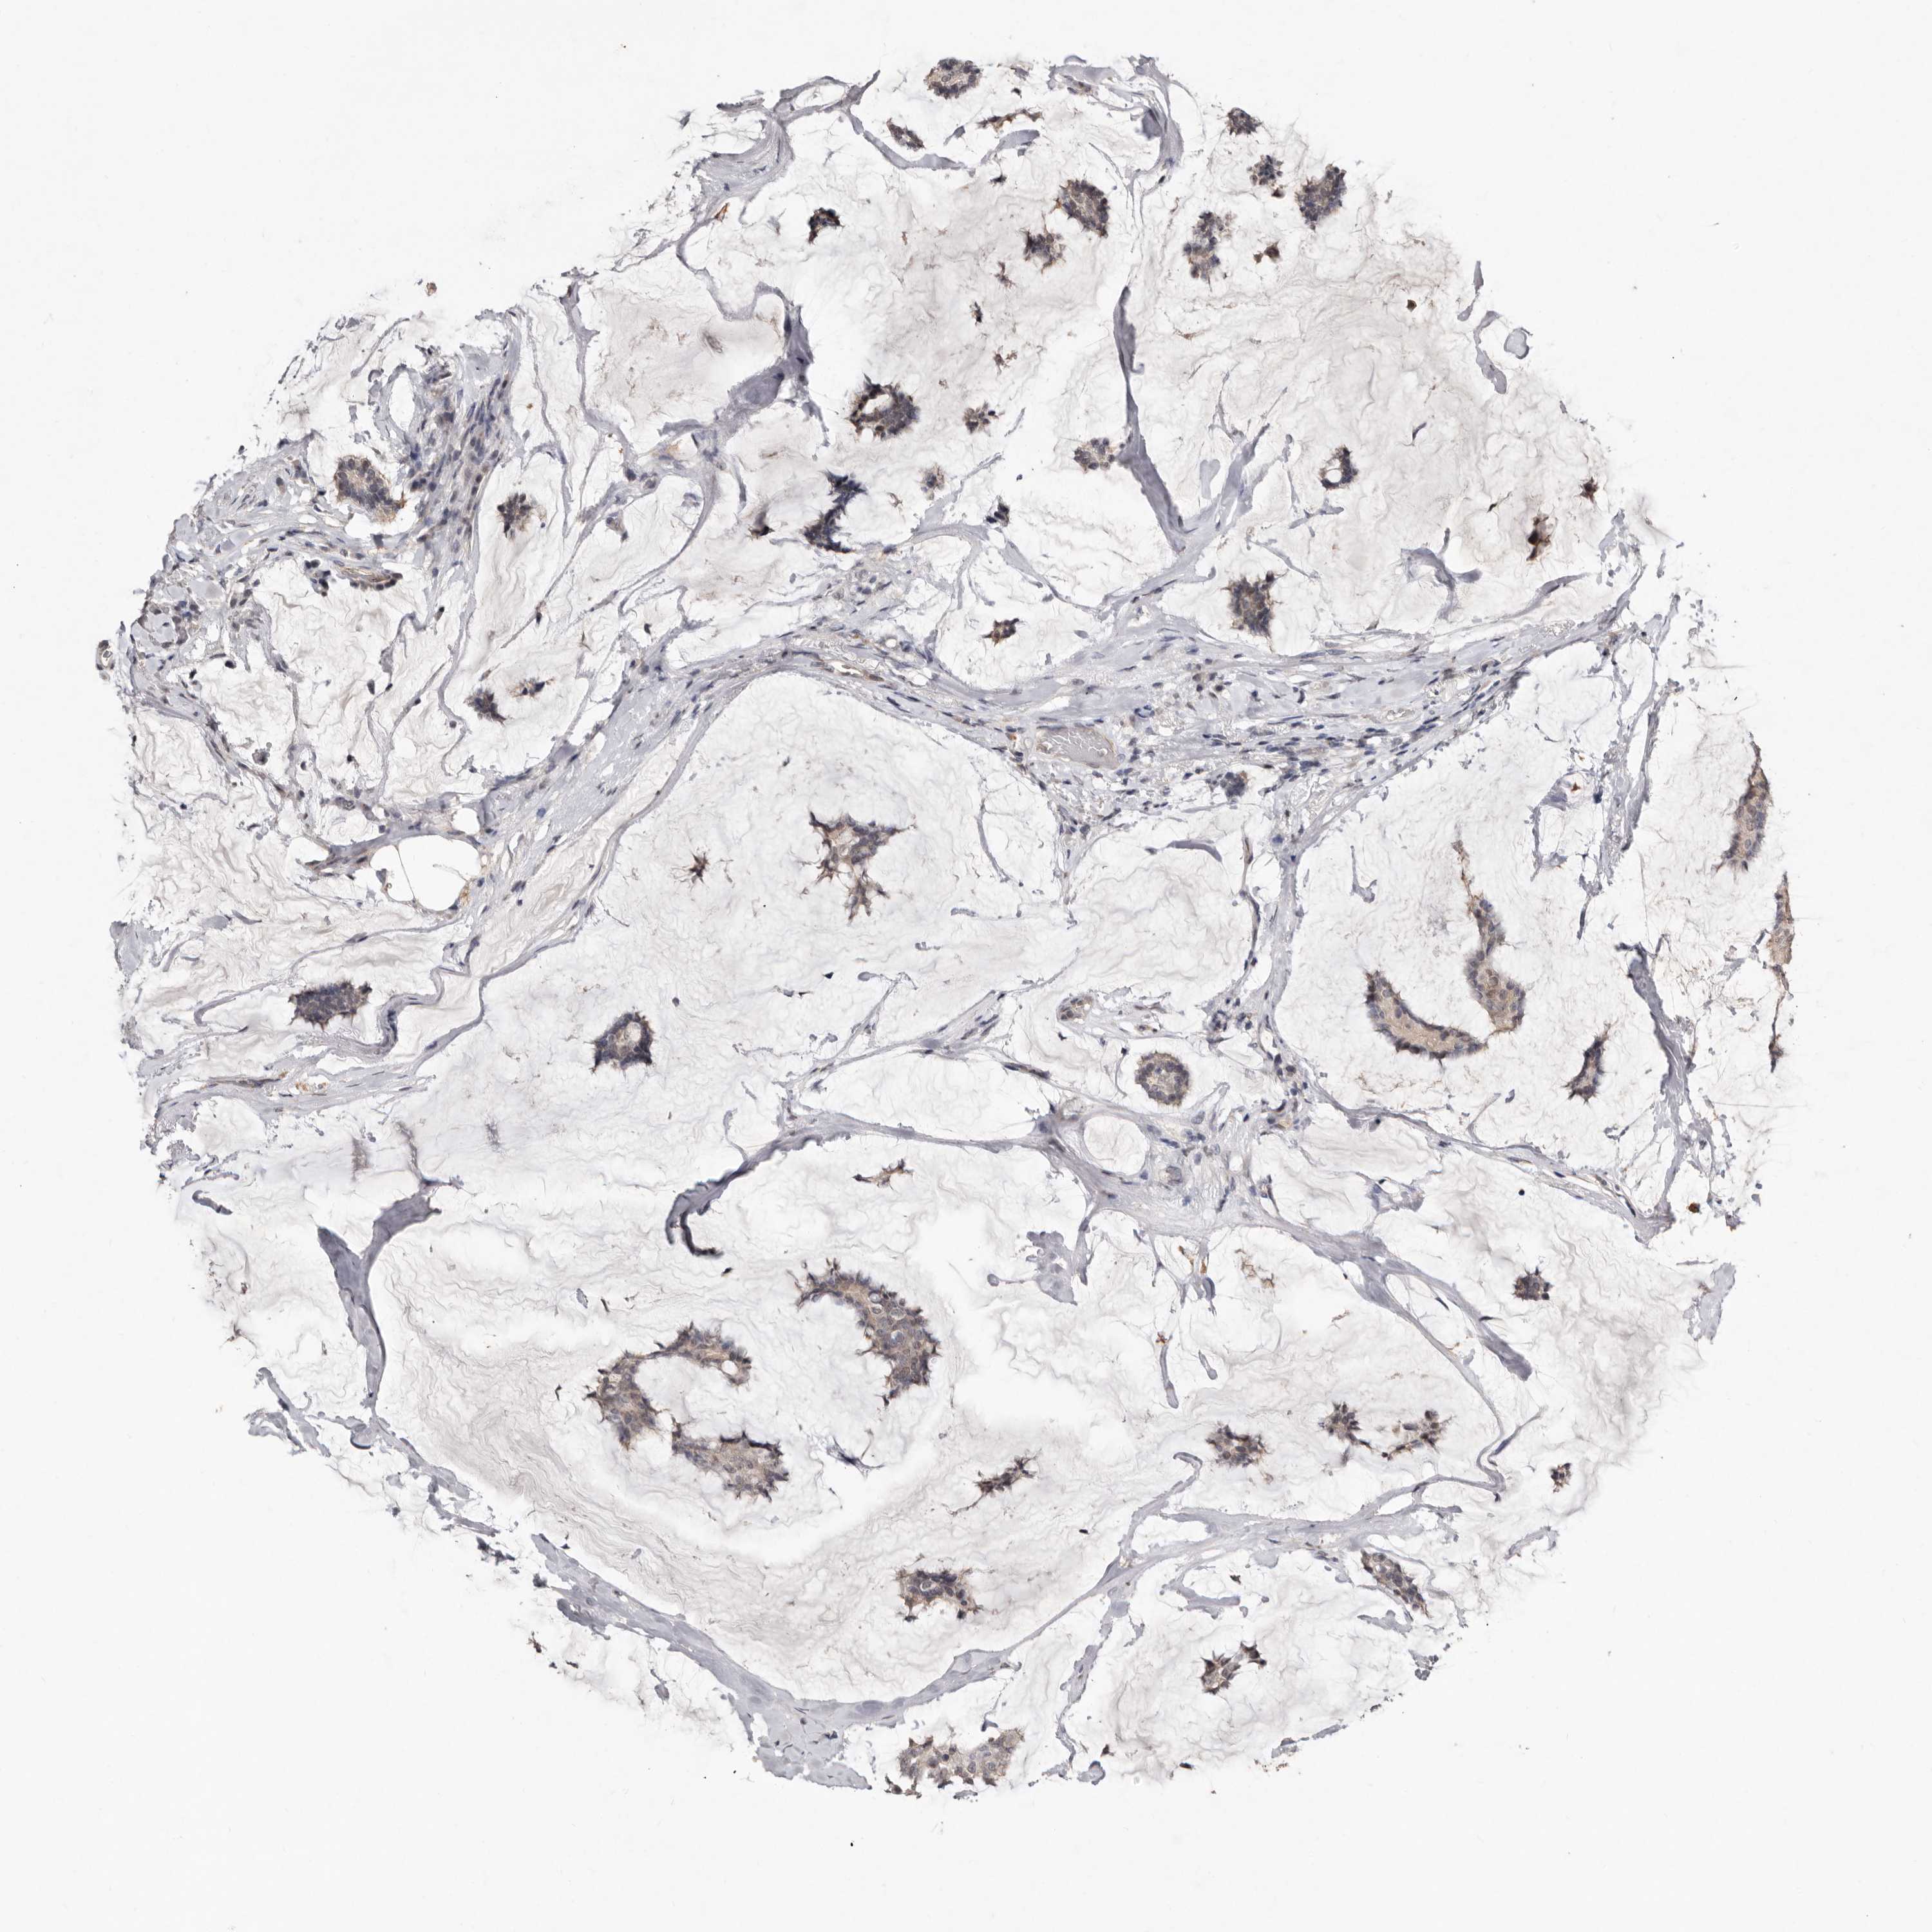

BRCA TCGA BRCA VALIDATION PROTEIN EXPRESSION